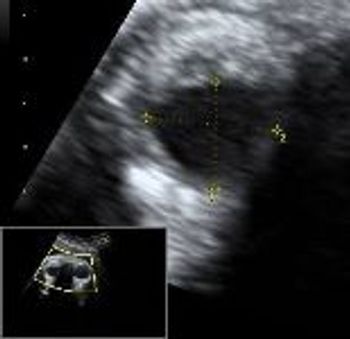

QUIZ: These images are of the jugular area in a first-trimester fetus. What do they tell you?